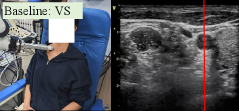

Figure 5: Real-World Experiment - Snapshots and ultrasound images, the red lines are the output of our pretrained regressor. No red line means the network can not detect the artery position. First row: UltraDP. (a) The policy began, and the artery was on the right of the image; (b) The policy output actions to guide the robot to make the artery center while going upwards; (c) The policy detected the bifurcation of the artery; (d) The external and internal arteries were clear in the image, and the scanning was over. Second row: Baseline, behavior cloning. (e)-(h): The BC policy (baseline 1) did not center the artery; And in the end, the policy drove the probe away from the neck, showing the unsatisfying generalization ability. Third row: Baseline, visual serving. (i)-(l) The VS controller (baseline 2) had the ability to center the artery; however, because some parameters like offset_z did not suit the female, the probe detached her neck, and the regressor couldn’t work when the image was incomplete; at last the probe kept going up, losing the image and hit her in the jaw.